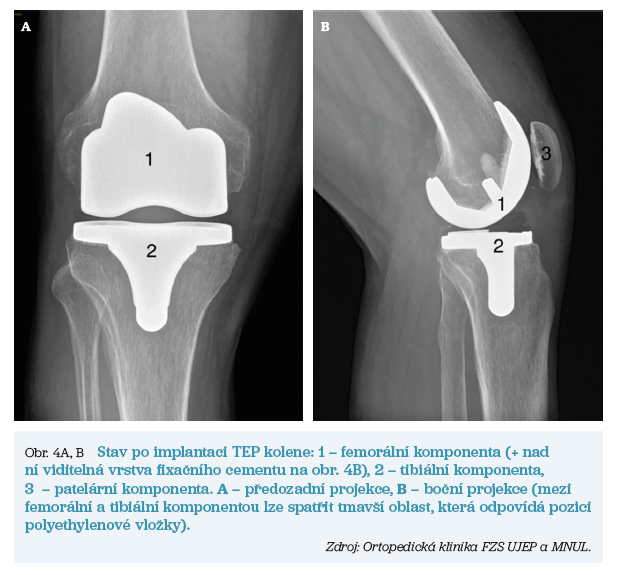

K pooperačnímu sledování pacienta je využíván pobyt na monitorovaném lůžku buď přímo v rámci lůžkových stanic ortopedického pracoviště, nebo eventuálně pak na pracovištích JIP (jednotka intenzivní péče) či ARO (anesteziologické a resuscitační oddělení). Již v časném pooperačním období může být dle zvyku daného pracoviště zahájena vertikalizace pacienta. Pooperačně je zcela zásadní dodržování opatření, která jsou shrnuta v tabulce 1. Těmito zásadami je nutné se řídit po dobu minimálně šesti týdnů od operace. Stav po úspěšné implantaci TEP kolene ukazuje obrázek 4.

- Femorální komponenta – tato součást je většinou slitinou různých kovů a je implantována na upravený povrch distální plochy femuru. K fixaci komponenty je nejčastěji použit kostní cement (polymethylmetakrylát) s možným obsahem antibiotik ke snížení rizika infekce.

- Tibiální komponenta – podobně jako u součásti femorální je i zde nejčastěji využita cementová fixace. Komponenta je implantována na kloubní plochu proximální tibie. Polyethylenová vložka je buď pevnou součástí kovové tibiální komponenty, nebo je s ní až následně spojena. Polyethylenová artikulační plocha slouží ke správnému posouvání shora naléhající komponenty femorální. Tím dosáhneme přesnějšího napodobení pohybu neporušeného kolenního kloubu.

- Patelární komponenta – patela je důležitou součástí kolenního kloubu a artróza se ani jí nevyhýbá. Proto, po částečné kostní resekci, můžeme v indikovaných případech provést i její náhradu polyethylenovou komponentou fixovanou kostním cementem.

Základní komponenty přehledně ukazuje obrázek 3.